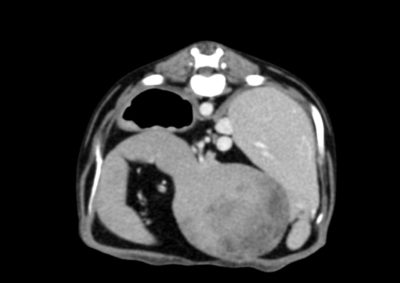

腫瘍外科 注意 ボタンをクリックした先に、治療中および手術中の画像が説明で使用されている場合がございます。 そのような画像に弱い方は閲覧なさらないようお願いいたします。 腫瘍外科 フレンチブルドッグ胃腺癌 胃部分切除 軟部組織外科腫瘍外科救急・集… 肝臓腫瘤破裂による腹腔内出血 腫瘍外科腫瘍内科 猫の直腸切除吻合 直腸リンパ腫 腫瘍外科 犬の肺腺癌の1例 腫瘍外科放射線治療 犬の軟部組織肉腫に対する腫瘍辺縁切除及び術後放射線療法 腫瘍外科 犬の肝細胞癌 軟部組織外科腫瘍外科 ジャックラッセルテリアの胃腫瘍 腫瘍外科 吻側下顎骨切除術〜メラノーマ〜 腫瘍外科 猫の上顎腫瘍切除 腫瘍外科 犬の脾臓腫瘤摘出 軟部組織外科腫瘍外科 大腸腺癌 軟部組織外科腫瘍外科 肺葉切除術 <1234567> 症例カテゴリー 放射線治療整形外科軟部組織外科脳神経外科内科腫瘍外科救急・集中治療リハビリテーション科腫瘍内科内視鏡科脳神経科呼吸器外科中医・漢方猫の腎移植循環器科